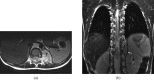

Neuroblastoma is one of the most common malignant neoplasms in childhood. The most common clinical presentation of this tumour is abdominal mass. However, affected children may have various clinical presentations as a result of disseminated metastatic disease or associated paraneoplastic syndromes at the time of diagnosis. In this article we have outlined the imaging findings in seven patients with "extra-abdominal" presentation of neuroblastoma and the pitfalls in making the correct diagnosis. The purpose of this pictorial review is to alert the general radiologist to the possible presentations of this common childhood malignancy to derive early detection and diagnosis.